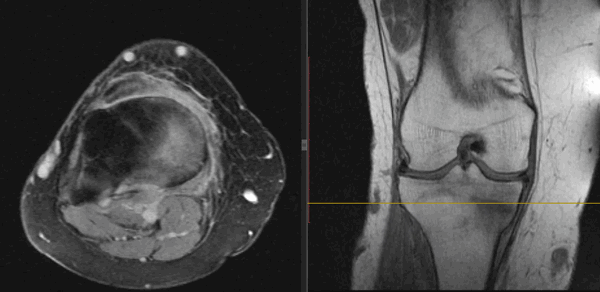

На Т2-ВИ в сагиттальной и корональной плоскостях определяется стресс-перелом дистальных отделов малоберцовой кости.

На Т2-fs-ВИ в сагиттальной плоскости определяется разрыва пяточного сухожилия.